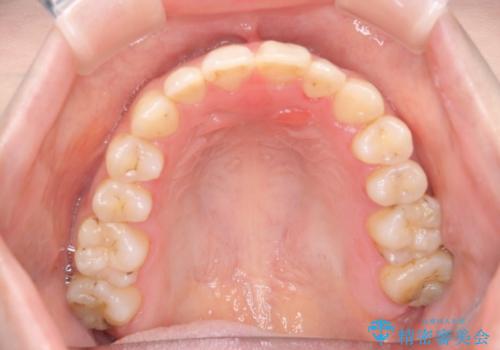

八重歯をインビザラインで非抜歯矯正

- 八重歯を主訴に来院されました。

インビザラインにて奥歯を後方に移動して八重歯が入るスペースを確保してく矯正する計画としました。

八重歯と前歯のガタガタがなくなり、歯並びがきれいになったのと、かみ合わせも改善することができました。